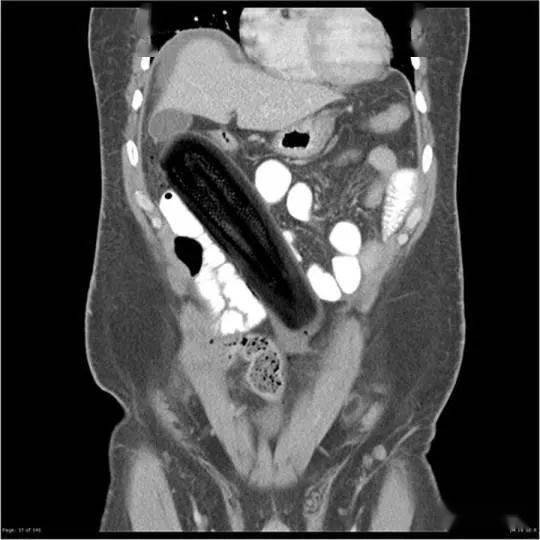

▷西葫芦在一位50岁男性的腹腔内 , 可以看到这颗19厘米长的蔬菜 , 顶端紧挨着胆囊 。研究这个案例的医生们发出了讨论:到底是使了多大劲儿 , 才能用一个圆钝的蔬菜怼到直肠穿孔 。